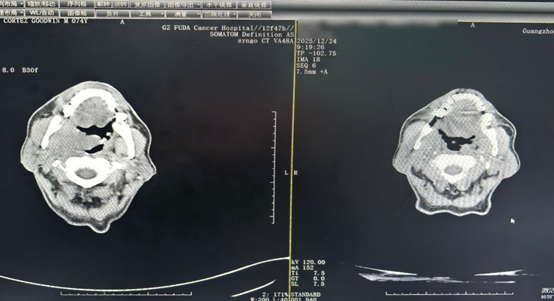

CT comparison after two treatment cycles showing reduction of oropharyngeal tumor and cervical masses